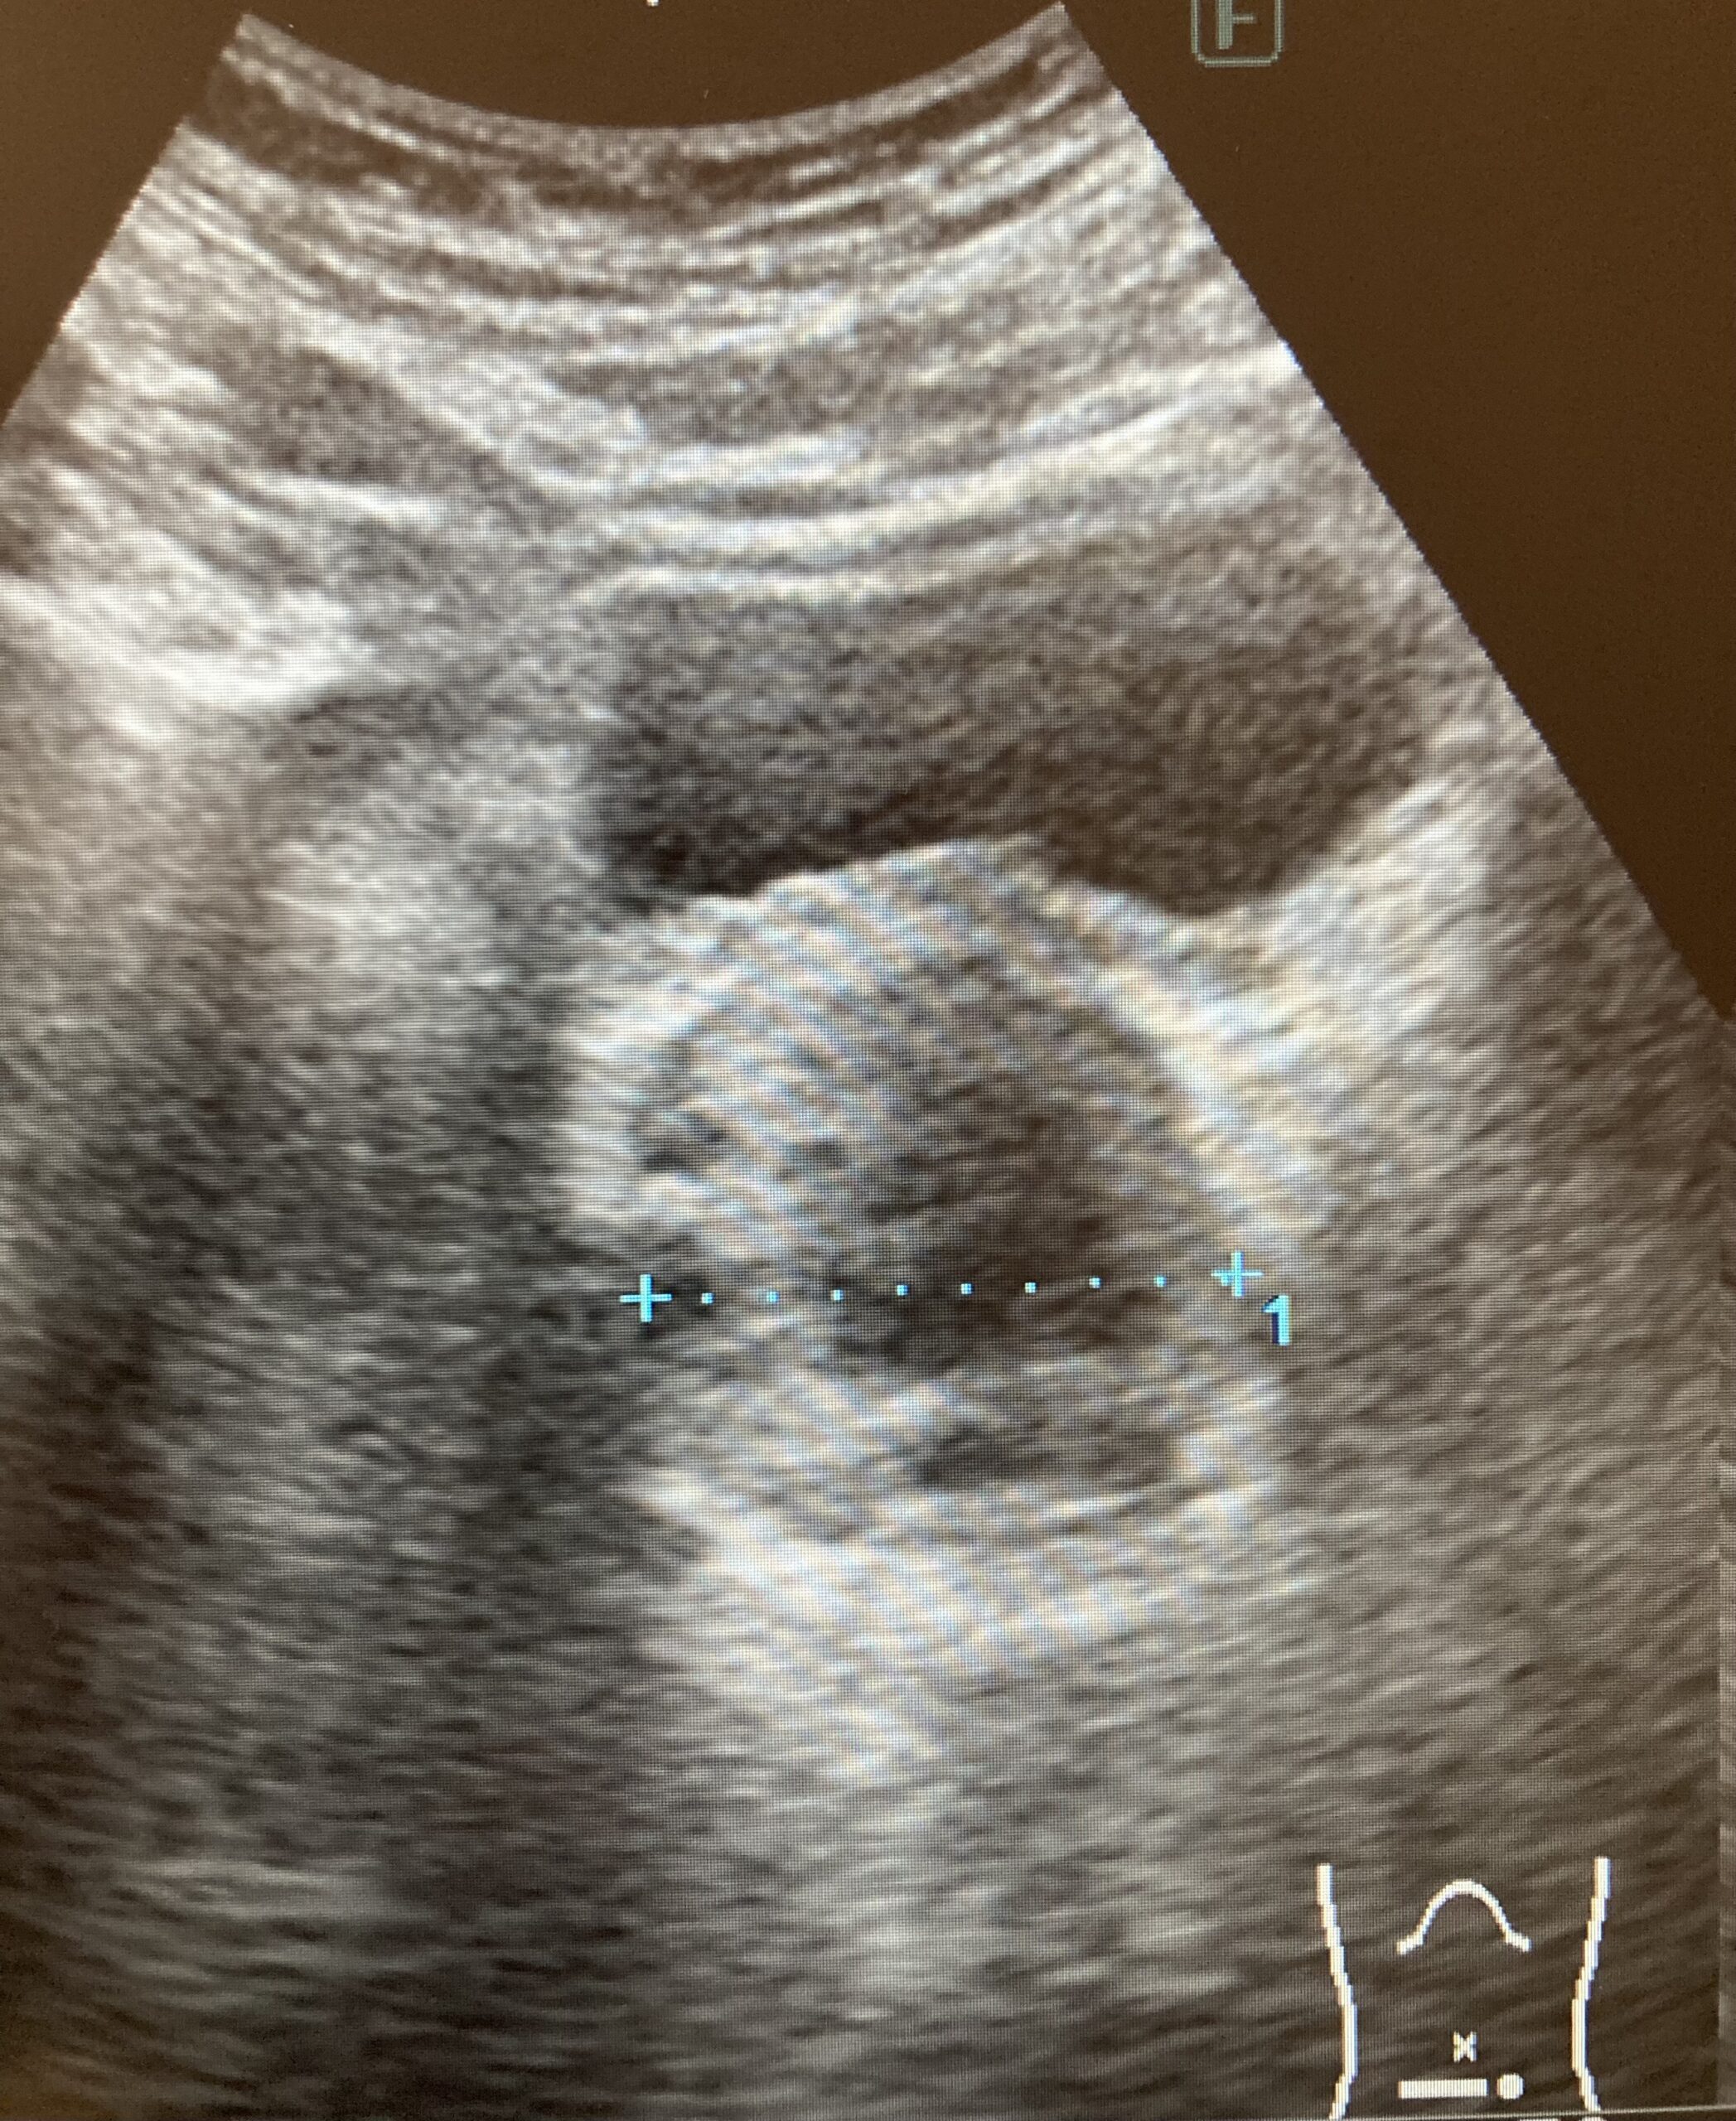

エコー検査では、残尿の量や、前立腺の大きさ、尿路に腫瘍や結石がないかどうかなどを見ていきます。

👆腎臓

👆前立腺と膀胱